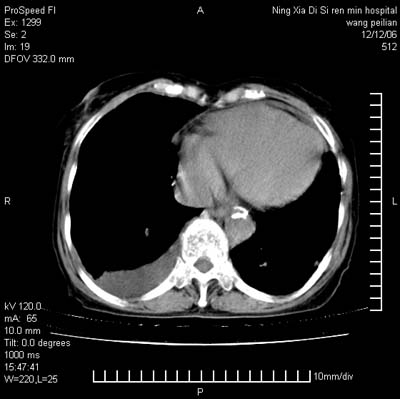

标题: CT5609:胸部:女77 病史不详 [打印本页]

标题: CT5609:胸部:女77 病史不详

两肺尖纤维索状影,两下肺结节块状影,且有钙化灶,右胸腔积液。考虑肺结核并胸膜炎。

双侧肺结核伴右侧胸腔积液.

两肺尖纤维索状影,两下肺结节块状影,且有钙化灶,右胸腔积液。考虑肺结核并胸膜炎肺间质纤维化

双肺见多个结节状及条索状影,双侧胸腔积液,右侧叶间积液,考虑结核性胸膜炎

肺结核并右侧结核性胸膜炎